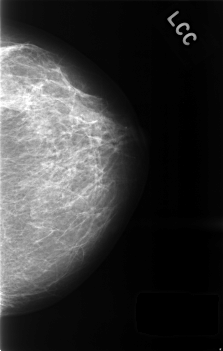

C_0436_1.LEFT_CC

LEFT_CC LINES 4560 PIXELS_PER_LINE 2896 BITS_PER_PIXEL 12 RESOLUTION 50 NON_OVERLAY

RIGHT_CC LINES 4568 PIXELS_PER_LINE 2872 BITS_PER_PIXEL 12 RESOLUTION 50 NON_OVERLAY